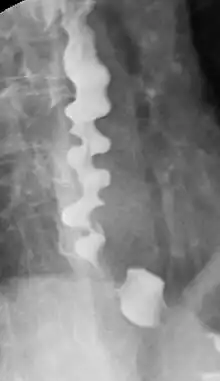

Corkscrew appearance of the esophagus.

Several radiographic findings are suggestive of DES, such as a "corkscrew esophagus" or "rosary bead esophagus" appearance on barium swallow x-ray, although these findings are not unique to DES.[2]